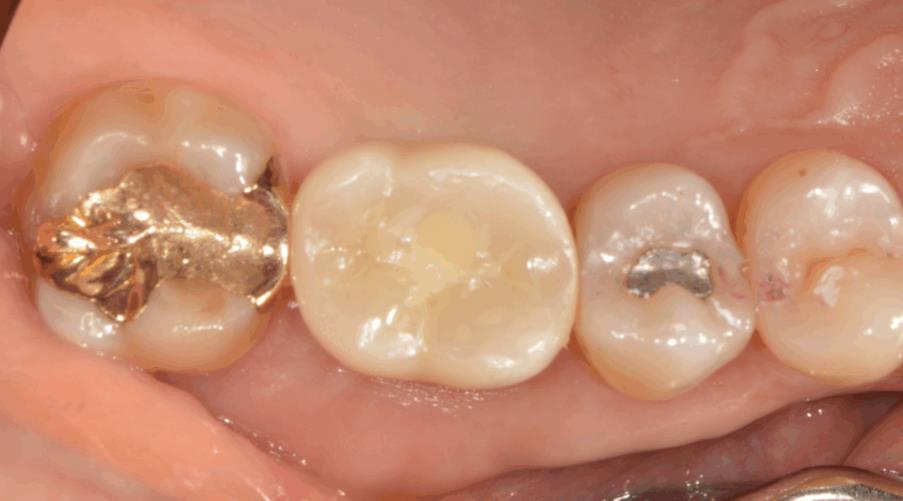

초진 구내사진 – 치아 결손으로 임플란트 치료 위해 내원하신 상태

보철물 장착 후 구내사진